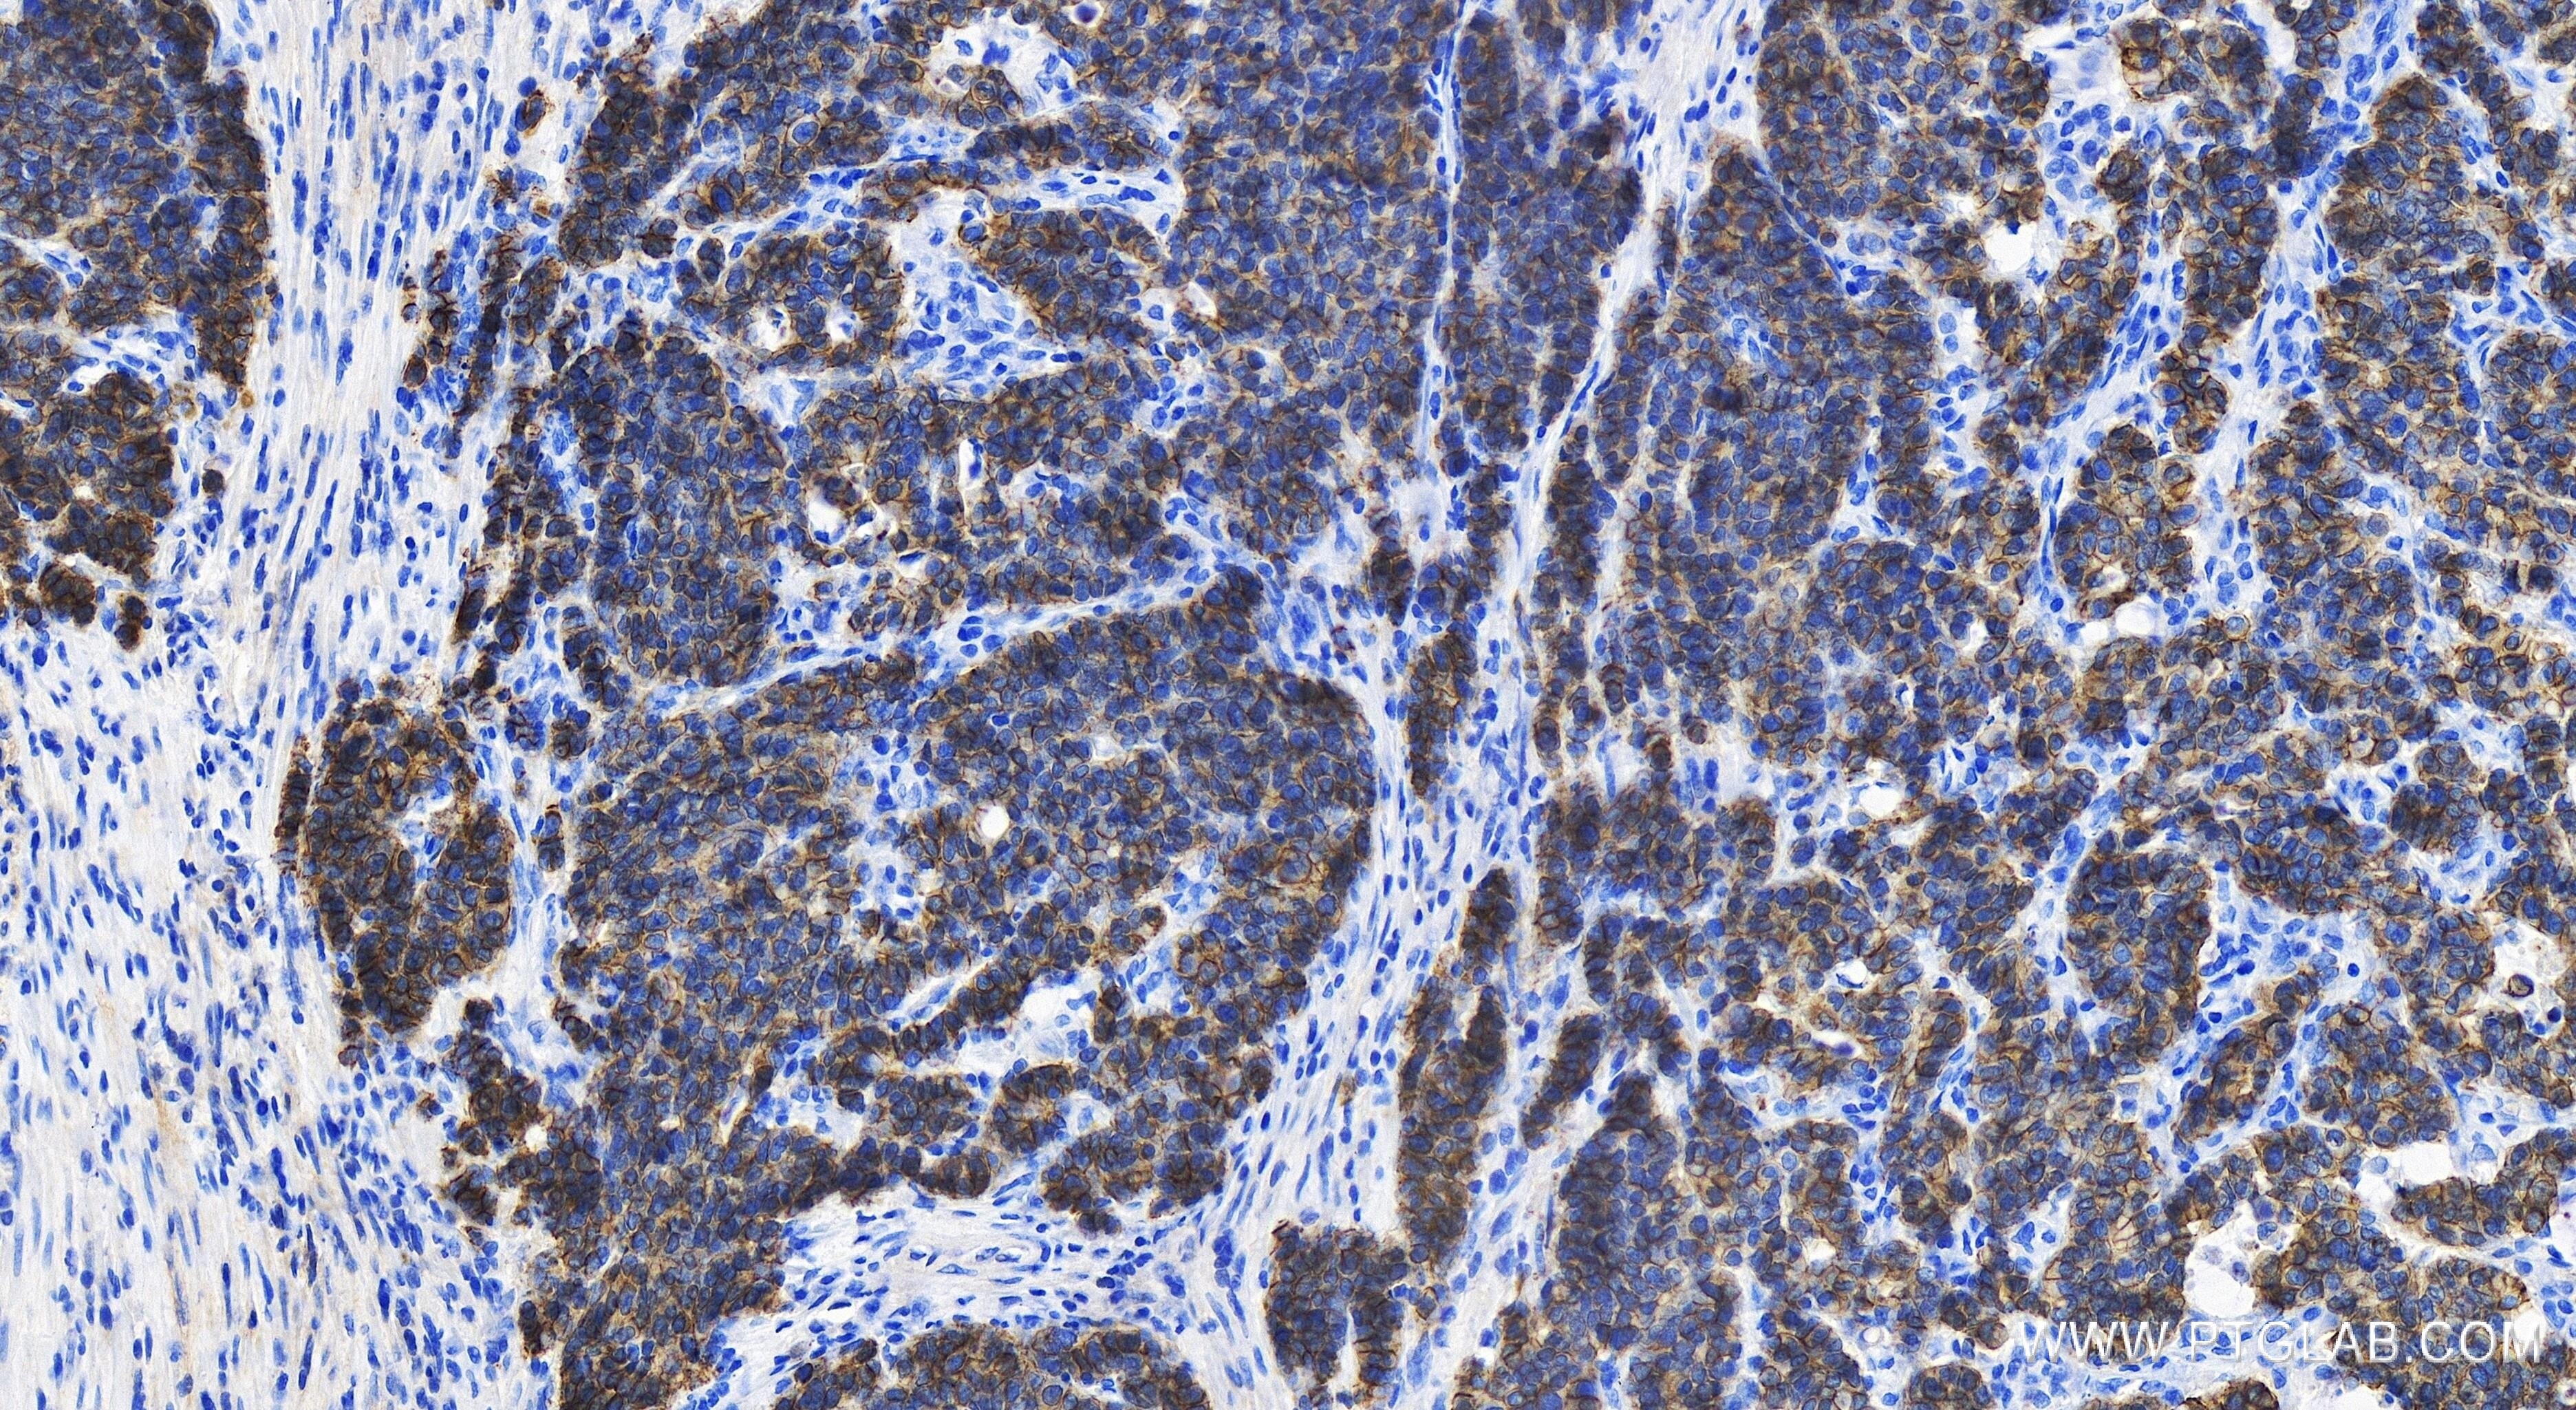

| Positive IHC detected in | human stomach cancer tissue, mouse skin tissue Note: suggested antigen retrieval with TE buffer pH 9.0; (*) Alternatively, antigen retrieval may be performed with citrate buffer pH 6.0 |

Cadherins are a family of transmembrane glycoproteins that mediate calcium-dependent cell-cell adhesion and play an important role in the maintenance of normal tissue architecture. E-cadherin (epithelial cadherin), also known as CDH1 (cadherin 1) or CAM 120/80, is a classical member of the cadherin superfamily which also include N-, P-, R-, and B-cadherins. E-cadherin is expressed on the cell surface in most epithelial tissues. The extracellular region of E-cadherin establishes calcium-dependent homophilic trans binding, providing specific interaction with adjacent cells, while the cytoplasmic domain is connected to the actin cytoskeleton through the interaction with p120-, α-, β-, and γ-catenin (plakoglobin). E-cadherin is important in the maintenance of the epithelial integrity, and is involved in mechanisms regulating proliferation, differentiation, and survival of epithelial cell. E-cadherin may also play a role in tumorigenesis. It is considered to be an invasion suppressor protein and its loss is an indicator of high tumor aggressiveness.